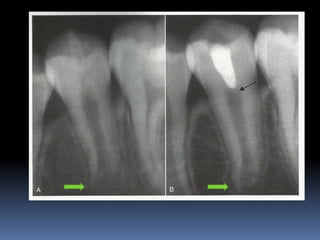

APEXOGENESIS

A

Vital Pulp Therapy procedure performed to encourage

continued physiologic development and formation of the root

end.

Since the main objective is to maintain the vitality of the

radicular pulp the pulp must be vital and capable of repair

Technique:

1. Anesthesia and rubber dam isolation

2. The inflamed pulp tissue is removed using a sharp round

bur in a high speed hand piece with water coolant for

superficial 2-3mm of pulp amputaion [Cvek pulpotomy]

3. Or removal of the entire pulp to the level of the canal

orifices using a large Spoon excavator

4. Hemorrhage is controlled by pressure on a cotton pellet

moistened with saline.

[ failure to achieve hemorrhage indicates pulpal inflammation]

The exposed pulp is rinsed with 2.5% sodium hypochlorite

MTA

or

hard set calcium hydroxide is placed over the

amputated pulp.

MTA is prepared by mixing MTA powder with saline in the

ratio of 3:1 on a glass slab. The mixture is placed on

the exposed pulp and patted with a moist cotton

pellet.

MTA sets in the presence of moisture. Wet cotton

pellet is placed over MTA and the tooth is restored.

The patient is then put on a periodic recall for 1-2yrs at

every 6 month interval.

Commonly encountered

•

Calcific metamorphosis

Internal resorption

In such cases NSRCT initiated.

APEXOGENESIS A Vital Pulp Therapyprocedure performed to encourage continued physiologic development and formation of the root end. Since the main objective is to maintain the vitality of the radicular pulp the pulp must be vital and capable of repair

Technique: 1. Anesthesia andrubber dam isolation 2. The inflamed pulp tissue is removed using a sharp round bur in a high speed hand piece with water coolant for superficial 2-3mm of pulp amputaion [Cvek pulpotomy] 3. Or removal of the entire pulp to the level of the canal orifices using a large Spoon excavator 4. Hemorrhage is controlled by pressure on a cotton pellet moistened with saline. [ failure to achieve hemorrhage indicates pulpal inflammation]

The exposed pulpis rinsed with 2.5% sodium hypochlorite MTA or hard set calcium hydroxide is placed over the amputated pulp. MTA is prepared by mixing MTA powder with saline in the ratio of 3:1 on a glass slab. The mixture is placed on the exposed pulp and patted with a moist cotton pellet. MTA sets in the presence of moisture. Wet cotton pellet is placed over MTA and the tooth is restored.

The patient isthen put on a periodic recall for 1-2yrs at every 6 month interval. Commonly encountered • Calcific metamorphosis • Internal resorption In such cases NSRCT initiated.